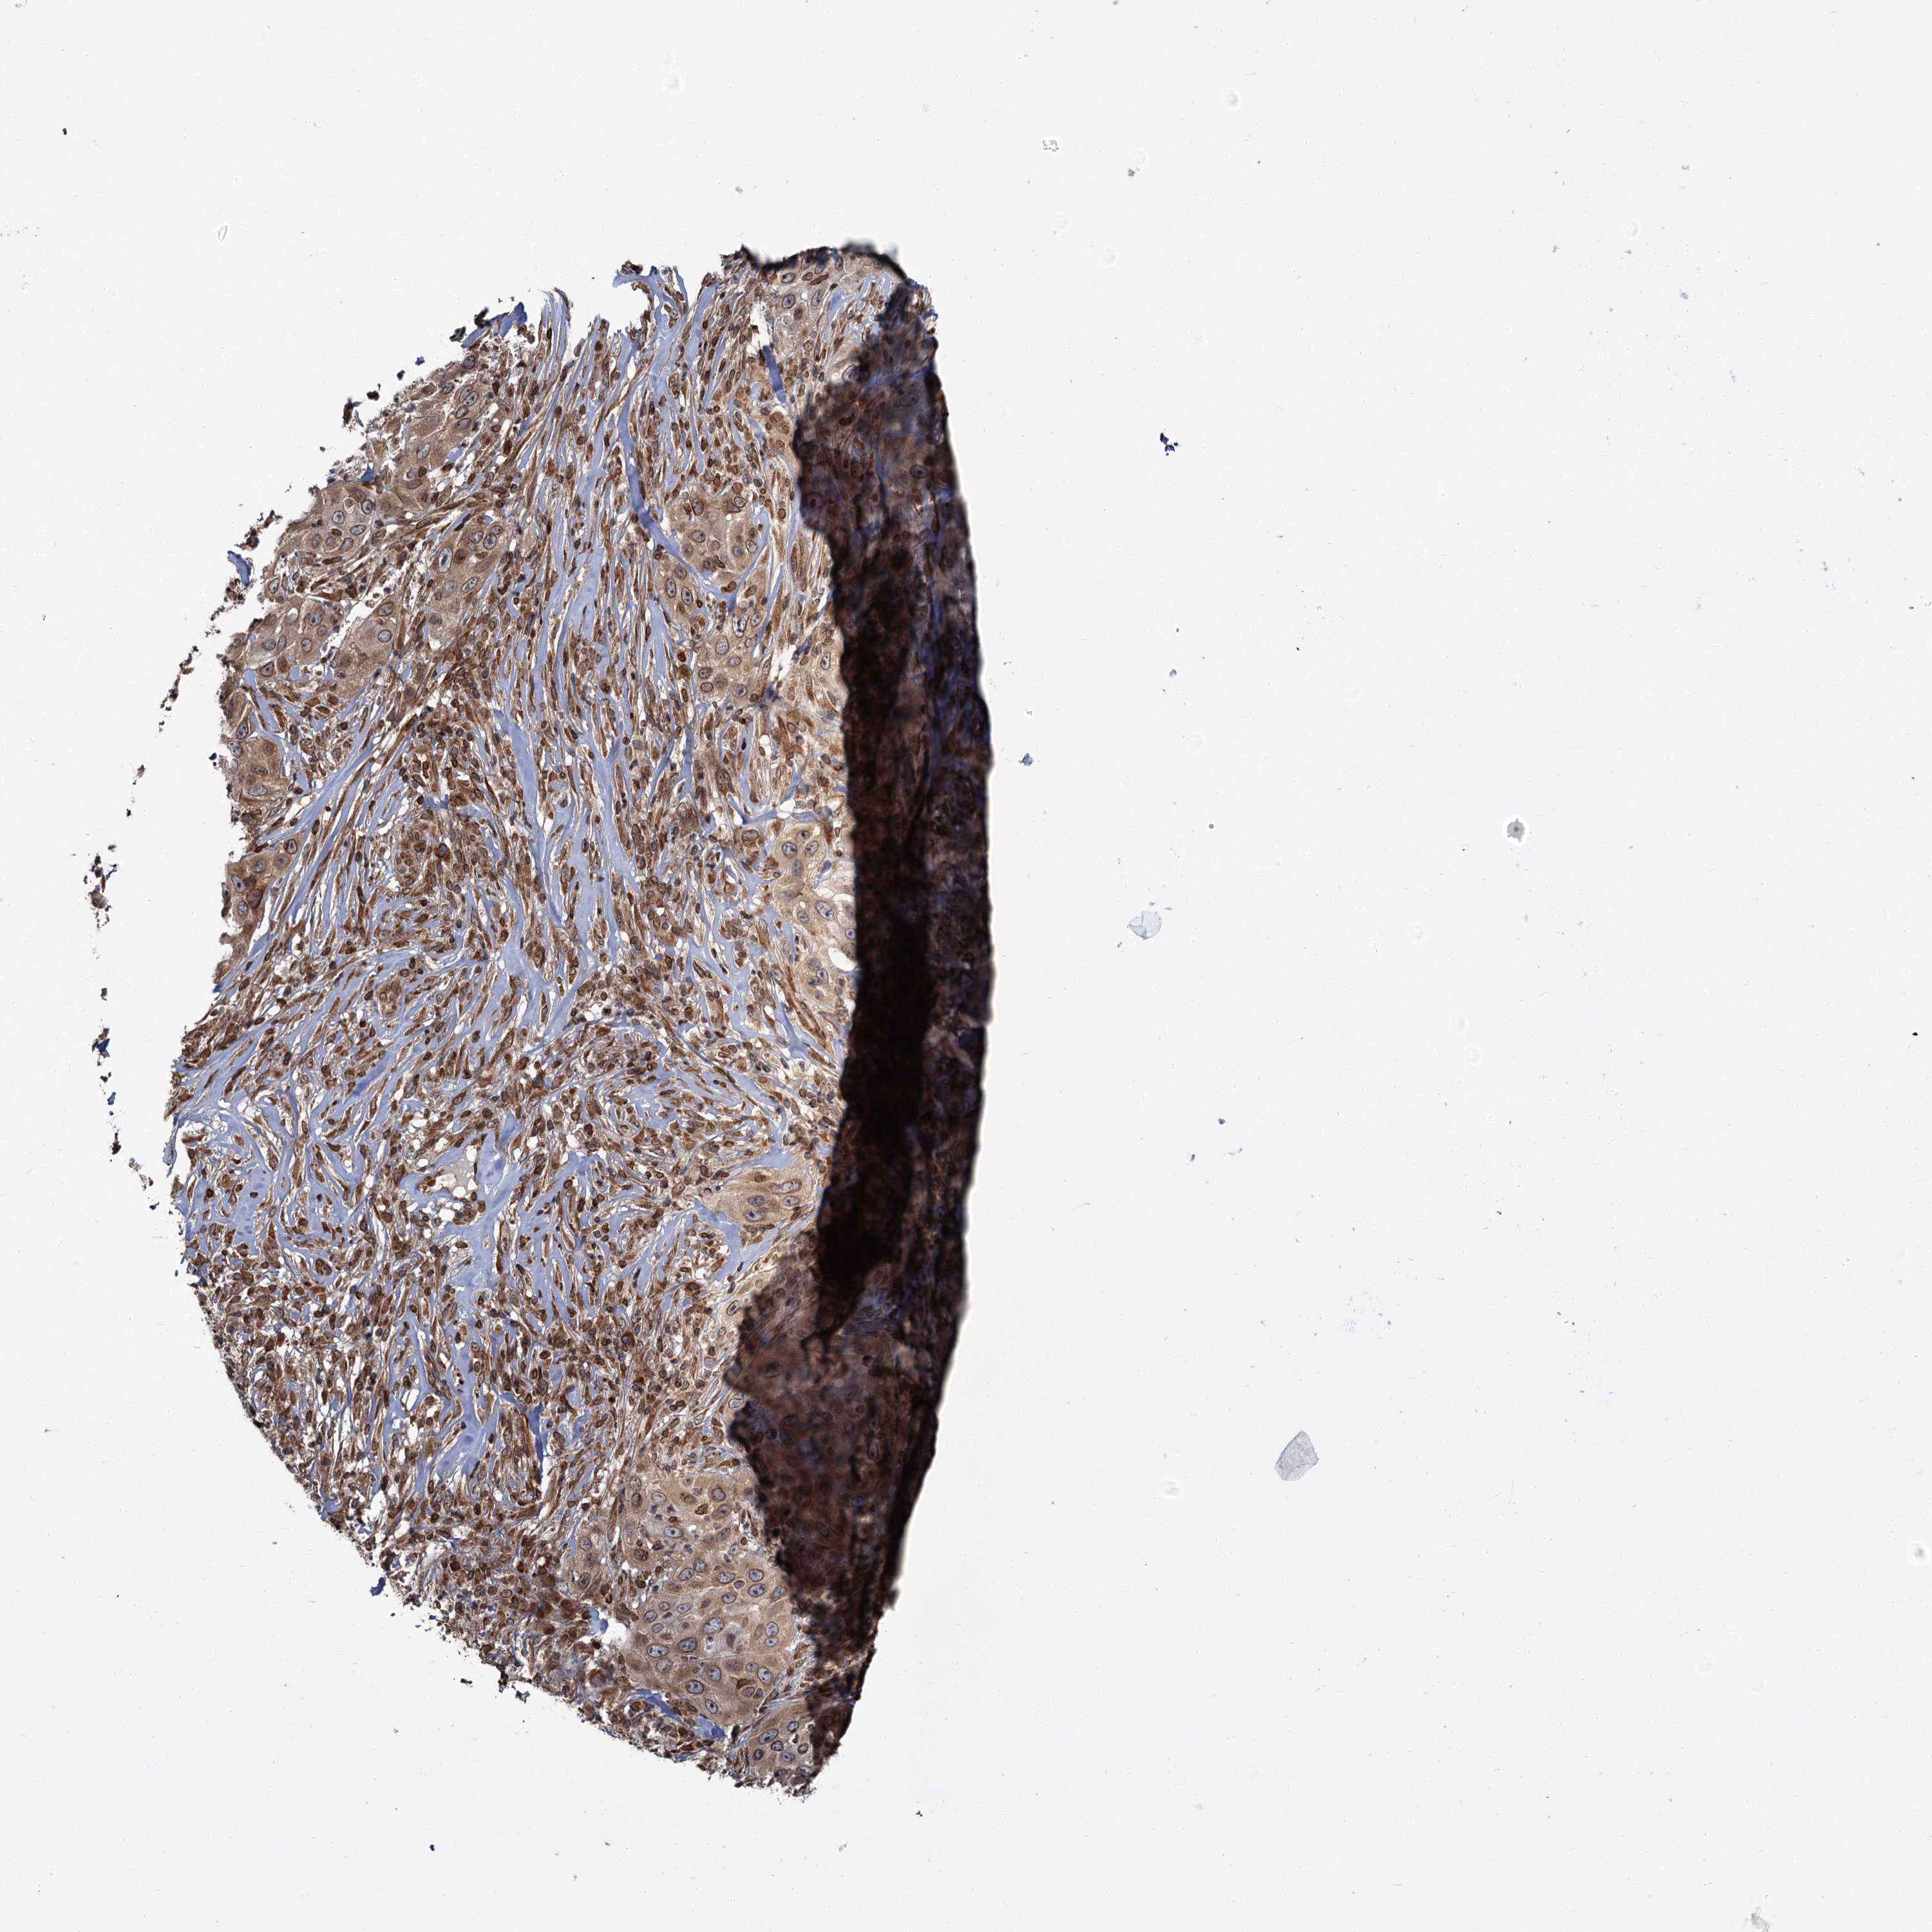

SKIN CANCER - Protein expressioni

A mouse-over function shows sample information and annotation data. Click on an image to view it in a full screen mode. Samples can be filtered based on level of antibody staining by selecting one or several of the following categories: high, medium, low and not detected. The assay and annotation is described here.

Each image is clickable and will lead to virtual microscopy that enables deeper exploration of all samples and also displays staining intensity scores, fraction scores and subcellular localization as well as patient and tissue information for each sample.

Antibody HPA037786

Basal cell carcinoma